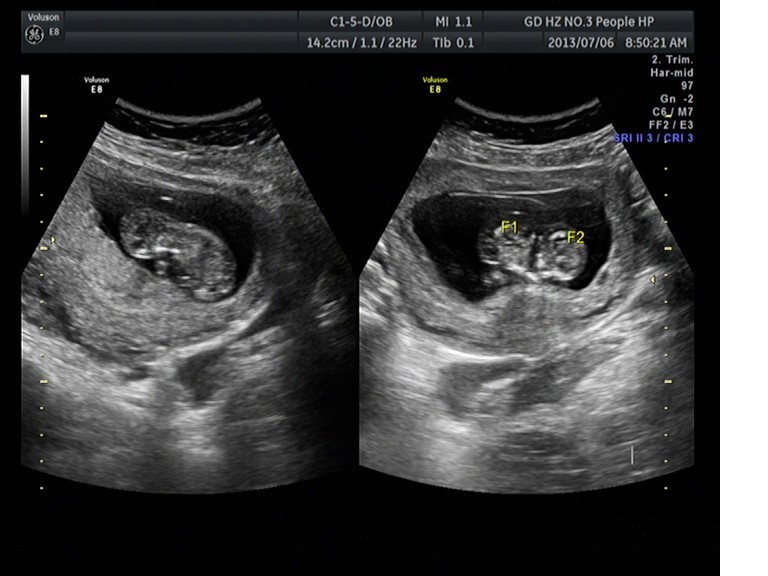

隨著環(huán)境污染日益嚴重,隨著各種地溝油的誕生,隨著各樣鎘大米的泛濫……我們的健康越來越受到威脅,很多疾病也隨之接踵而至,胎兒先天性疾病也越來越多見。7月6日,我院超聲科王瑤醫(yī)生在做胎兒產(chǎn)前NT篩查中發(fā)現(xiàn)一例孕約11周+的聯(lián)體雙胎。超聲所見:增大的子宮內(nèi)可見聯(lián)體雙胎兒回聲,可見兩個胎頭不能分離,胸部及腹部融合,可見一個增大的心臟。

聯(lián)體嬰兒B超圖像